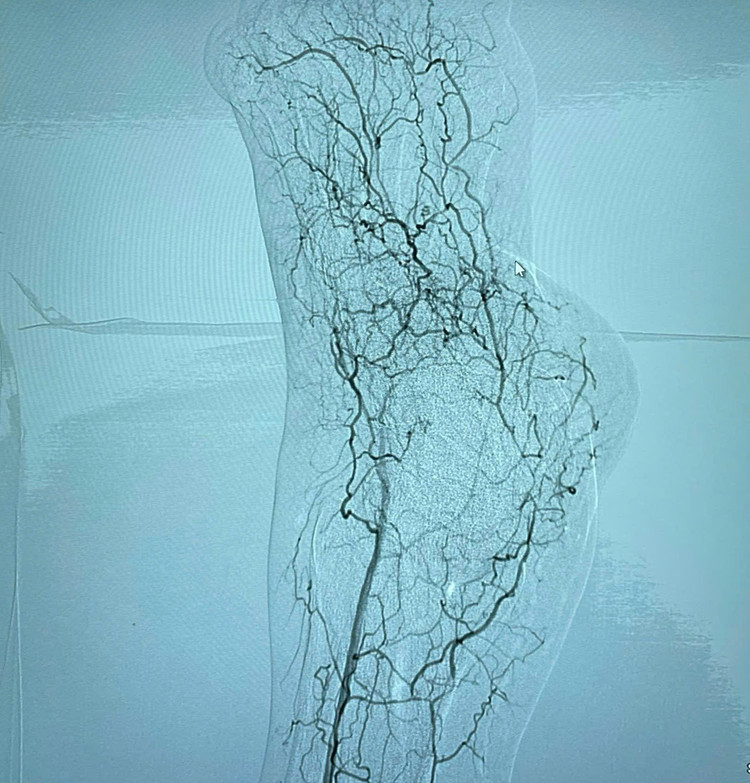

Kết quả chụp cắt lớp động mạch chi dưới cho thấy người bệnh bị tắc động mạch đùi nông chân trái, cấp máu bàn chân trái giảm nặng. Các bác sĩ đã tiến hành chụp mạch số hóa xóa nền (chụp mạch DSA) để xác định vị trí và mức độ tổn thương tắc động mạch đùi nông, ngay sau đó người bệnh đã được nong bóng và đặt stent tại vị trí hẹp tắc.

Kết quả chụp kiểm tra sau can thiệp cho thấy động mạch đùi nông đã được tái thông hoàn toàn, cấp máu cho bàn chân trái tốt, tình trạng người bệnh được cải thiện chân trái giảm phù nề, đỡ đau nhức.

| Động mạch của người bệnh bị tắc trước can thiệp (vị trí mũi tên chỉ) và sau can thiệp - Ảnh BVCC |